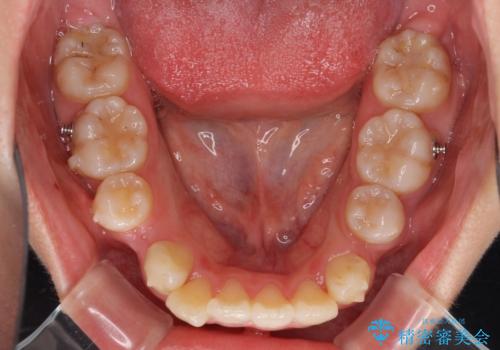

インビザラインによる矯正治療は、どれだけマウスピースを外す時間を短くできるかが成功の鍵となりますが、抜歯矯正ではよりシビアに要求されます。

こちらの患者様は、1日22時間以上を厳守してくださり、3年強で終えることができました。